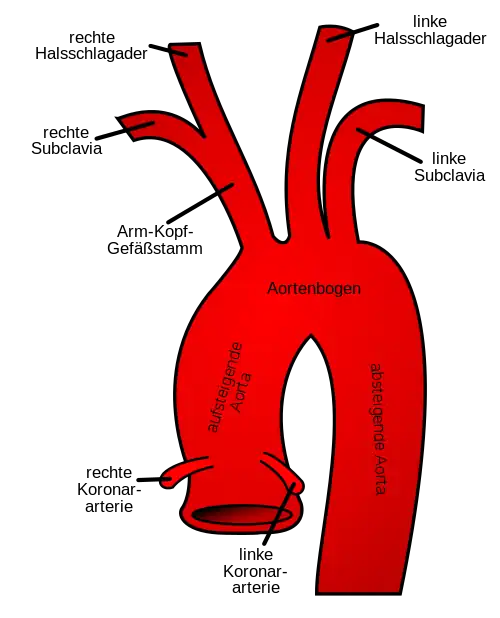

- Aufsteigende Aorta (Aorta ascendens), die von der linken Herzkammer aus nahezu senkrecht nach oben verläuft und von dieser durch die Aortenklappe getrennt ist. Sie liegt vollständig in der Herzbeutelhöhle und ist nur wenige Zentimeter lang. Der leicht bauchig erweiterte Anfangsteil der Aorta (Aortenbulbus oder Bulbus aortae) besteht aus den drei Sinus aortae (auch Sinus Valsalvae), die vom Schließungsrand des jeweiligen Aortenklappensegels und der Aortenwand begrenzt sind. Aus dem vorderen und linken Sinus entspringen unmittelbar am Herzen die Herzkranzgefäße (Arteriae coronariae) zur Versorgung des Herzmuskels. An der aufsteigenden Aorta befindet sich eine Umschlagstelle des Herzbeutels, die als Crista aortae ascendentis (Rindfleischfalte) bezeichnet wird.

- Aortenbogen (Arcus aortae) als Fortsetzung der senkrecht aufsteigenden Aorta. Aus dem Aortenbogen gehen unter anderem die Schlagadern zur Versorgung von Kopf und Armen ab. Die drei wichtigsten Abgänge des Aortenbogens sind der Truncus brachiocephalicus, die Arteria carotis communis sinistra und die Arteria subclavia sinistra.